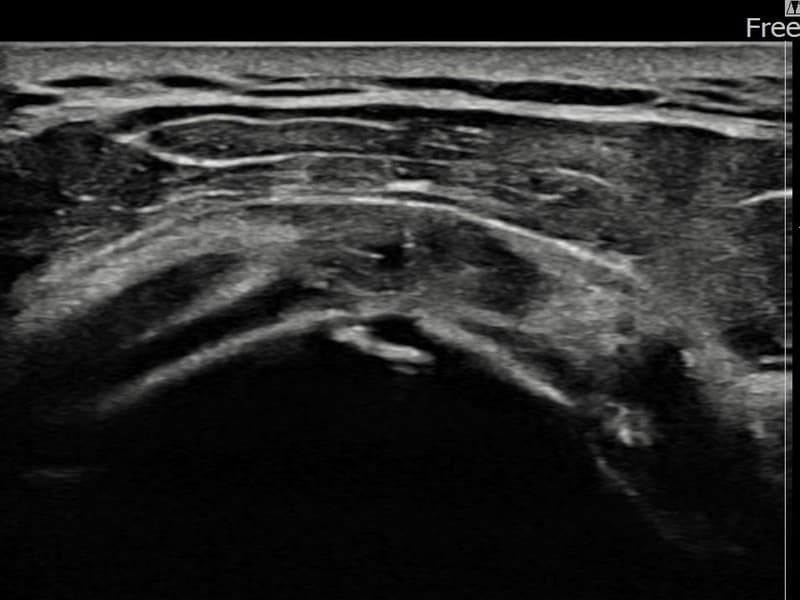

시술 전 초음파 측정 결과 파열 크기는 8mm × 3mm (힘줄 두께의 약 33% 결손)로 확인되었습니다. 시술 전 초음파에서 좌측 극상근건 관절면측의 에코 단절과 힘줄 내 저에코 결손이 확인되었습니다. 시술 후 초음파에서 파열 부위가 재생 조직으로 채워지고 힘줄 에코 패턴이 정상화된 것이 관찰되었습니다.

60대 중반 남성 환자분으로, 왼쪽 어깨 통증이 수개월간 지속되다가 최근 야간 통증까지 생겨 내원하셨습니다. 활동적인 생활을 즐기시는 분으로 통증으로 인해 운동이나 취미 활동에 제약이 생기셔서 비수술 치료를 강력히 원하셨습니다. 초음파 검사에서 좌측 극상근건 관절면측 부분파열이 확인되었으며, 초음파 유도 하 축소봉합술을 시행하였습니다. 시술 후 단계적으로 재활 운동을 진행하였고, 10주 후 추적 초음파에서 파열 부위가 재생 조직으로 채워지고 힘줄 연속성이 회복되어 정상 생활에 복귀하셨습니다.